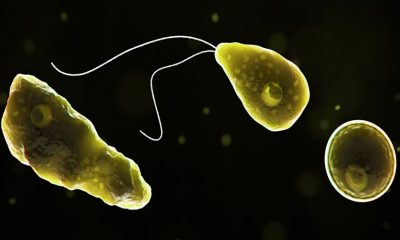

Nos EUA, houve 143 casos de infectados e apenas quatro pessoas sobreviveram